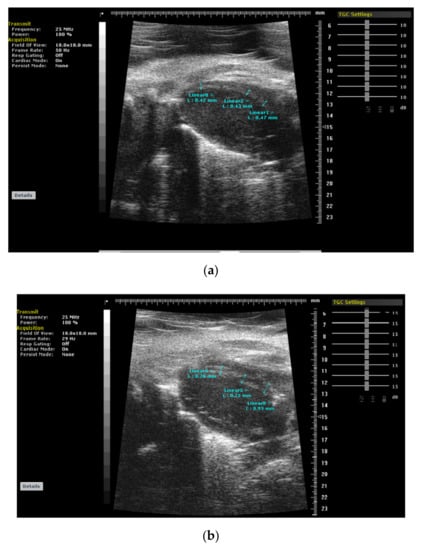

2. Basal Septal Hypertrophy and Clinic Observations

3. BSH and Animal Validation Studies

Striking Difference between Animal and Human BSH Data